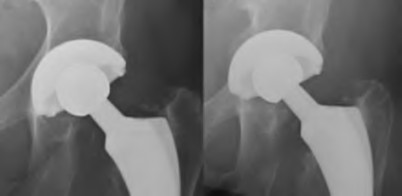

The radiograph demonstrates a periprosthetic femur fracture extending to the tip of the stem. The long spiral fracture is consistent with a loose implant. The bone stock is sufficient. Therefore, this fracture pattern would classify as a B2 using the Vancouver classification system. The Vancouver classification for periprosthetic femoral fractures is simple yet incorporates all the pertinent factors such a location, stem fixation, and bone stock. Type A is a trochanteric fracture- lesser or greater. These can be treated non-operatively usually and ORIF if symptomatic. Type B fractures are around or just below the stem and are subdivided into three types. Type B1 is a fracture with a well fixed stem.

The treatment is cable plating or allograft struts or a combination of the two. Type B2 is a fracture with a loose stem with good bone stock. The treatment is a cementless porous coated long stem atleast two diameter length past the

fracture site. Type B3 is a fracture with a loose stem and comminution. For younger patients, use cementless porous coated long stems with allograft struts. For older patients, consider a tumor prosthesis. Cement fixation is sometimes necessary Type C is a fracture well below the stem tip. These can be treated independently of the prosthesis.

Springer et al showed optimal outcomes with revision involving long extensively-coated femoral stems for Vancouver B fractures.

Masri et al review the classification and treatment of periprosthetic femur fractures.